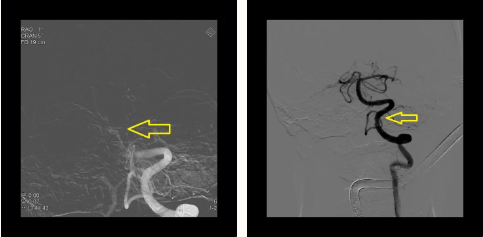

情况危急,赵主任与团队反复研究并征得家属同意后,立即进行手术治疗。当日13:00王大爷在全麻下行急诊支架取栓手术,13:54取栓手术成功。术中取出大量栓子, 基底动脉恢复畅通。

术后2小时老人恢复清醒,第二天拔出气管插管,转危为安。现在的王大爷神志清醒,问答合理,四肢活动自如,每次看到为他做了两次取栓手术的赵主任都感动不已!